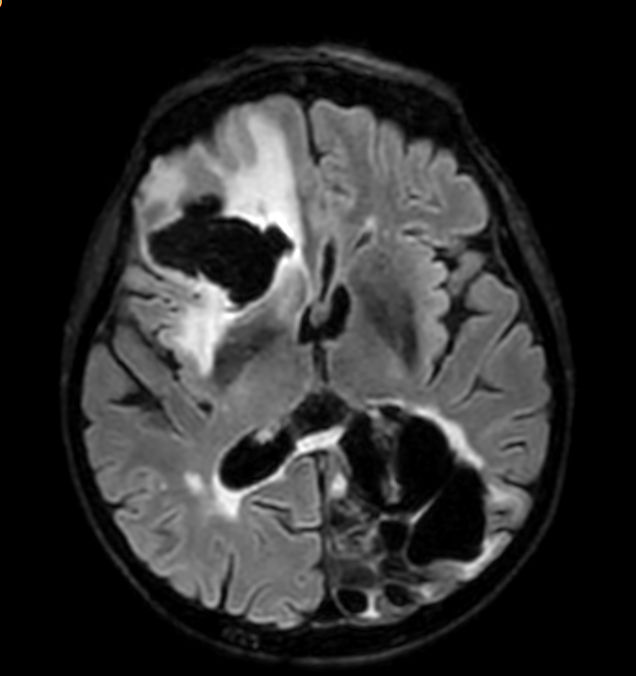

Axial SWIp (Modulus)

Axial SWIp (minIP)

Axial SWIp (Phase)